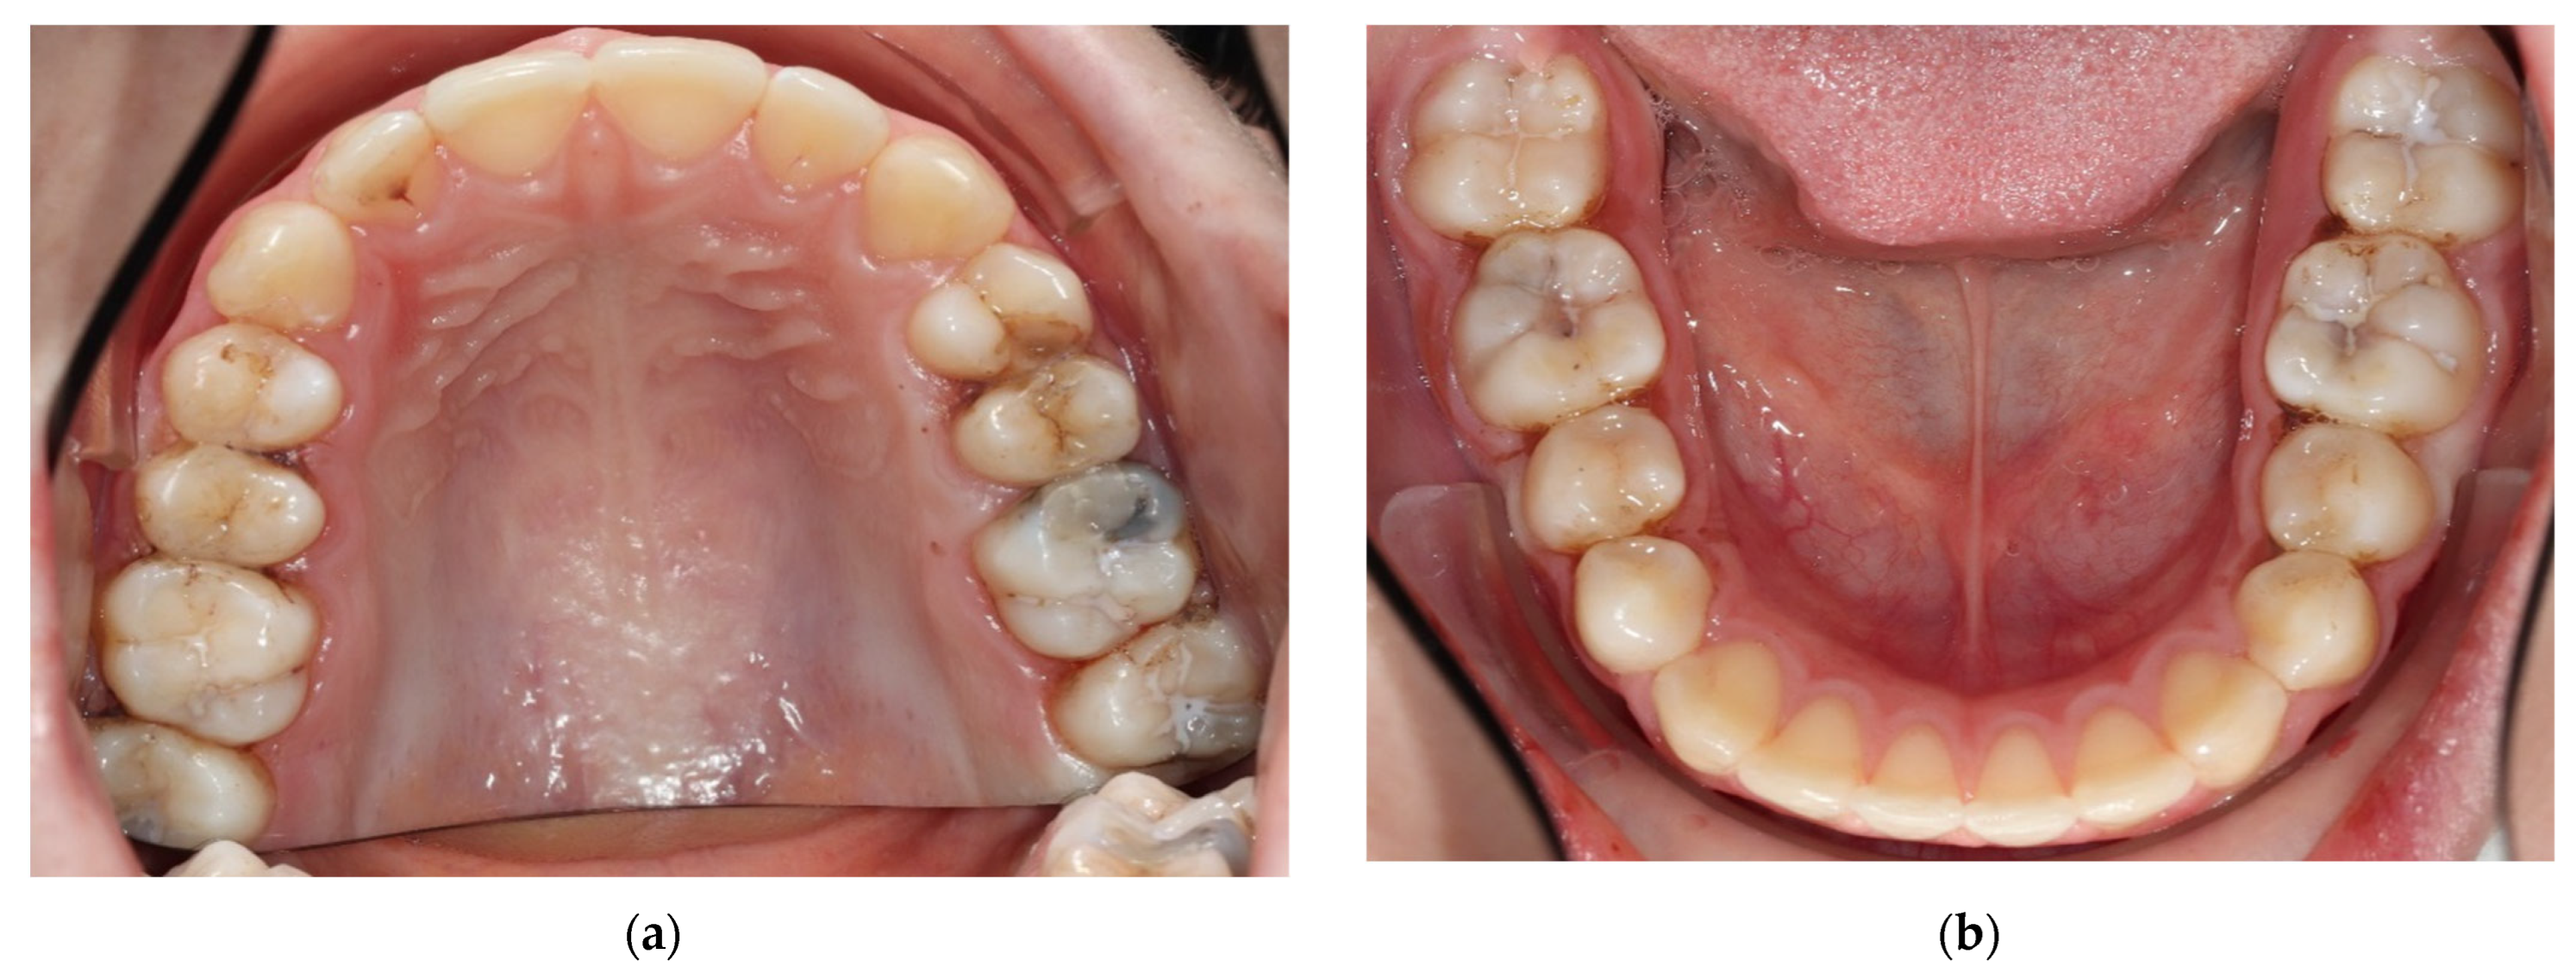

- Tooth separation with orthodontic rubbers: This revealed the absence of cavitation (Figure 3a,b).